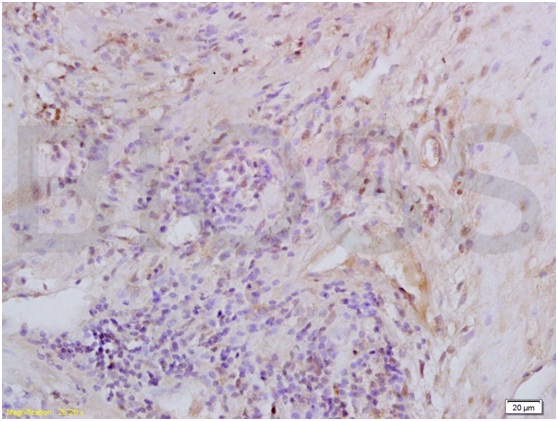

Tissue/cell: mouse uterus tissue; 4% Paraformaldehyde-fixed and paraffin-embedded; Antigen retrieval: citrate buffer ( 0.01M, pH 6.0 ), Boiling bathing for 15min; Block endogenous peroxidase by 3% Hydrogen peroxide for 30min; Blocking buffer (normal goat serum,C-0005) at 37℃ for 20 min; Incubation: Anti-MIP2/GRO Beta/CXCL2 Polyclonal Antibody, Unconjugated(bs-1162R) 1:200, overnight at 4℃, followed by conjugation to the secondary antibody(SP-0023) and DAB(C-0010) staining